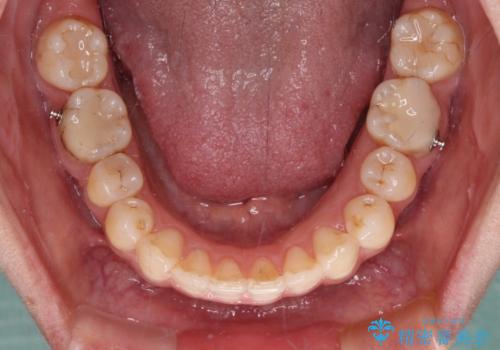

- 下顎の前歯が隠れていることと、デコボコを気にして来院された患者様です。

銀歯やムシ歯処置の必要な歯が奥歯にあり気になっていたので、矯正治療の途中でセラミッククラウンへ変更し、その後歯列を仕上げていくこととしました。

咬み合わせと目立っていた銀歯が改善され、患者様には大変満足していただきました。